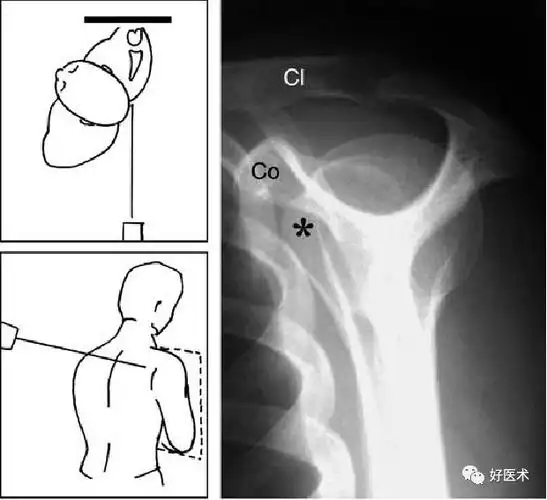

肩痛康复肩关节损伤影像诊断技巧

肩关节x线检查体位大全

不同肩关节x线投照位